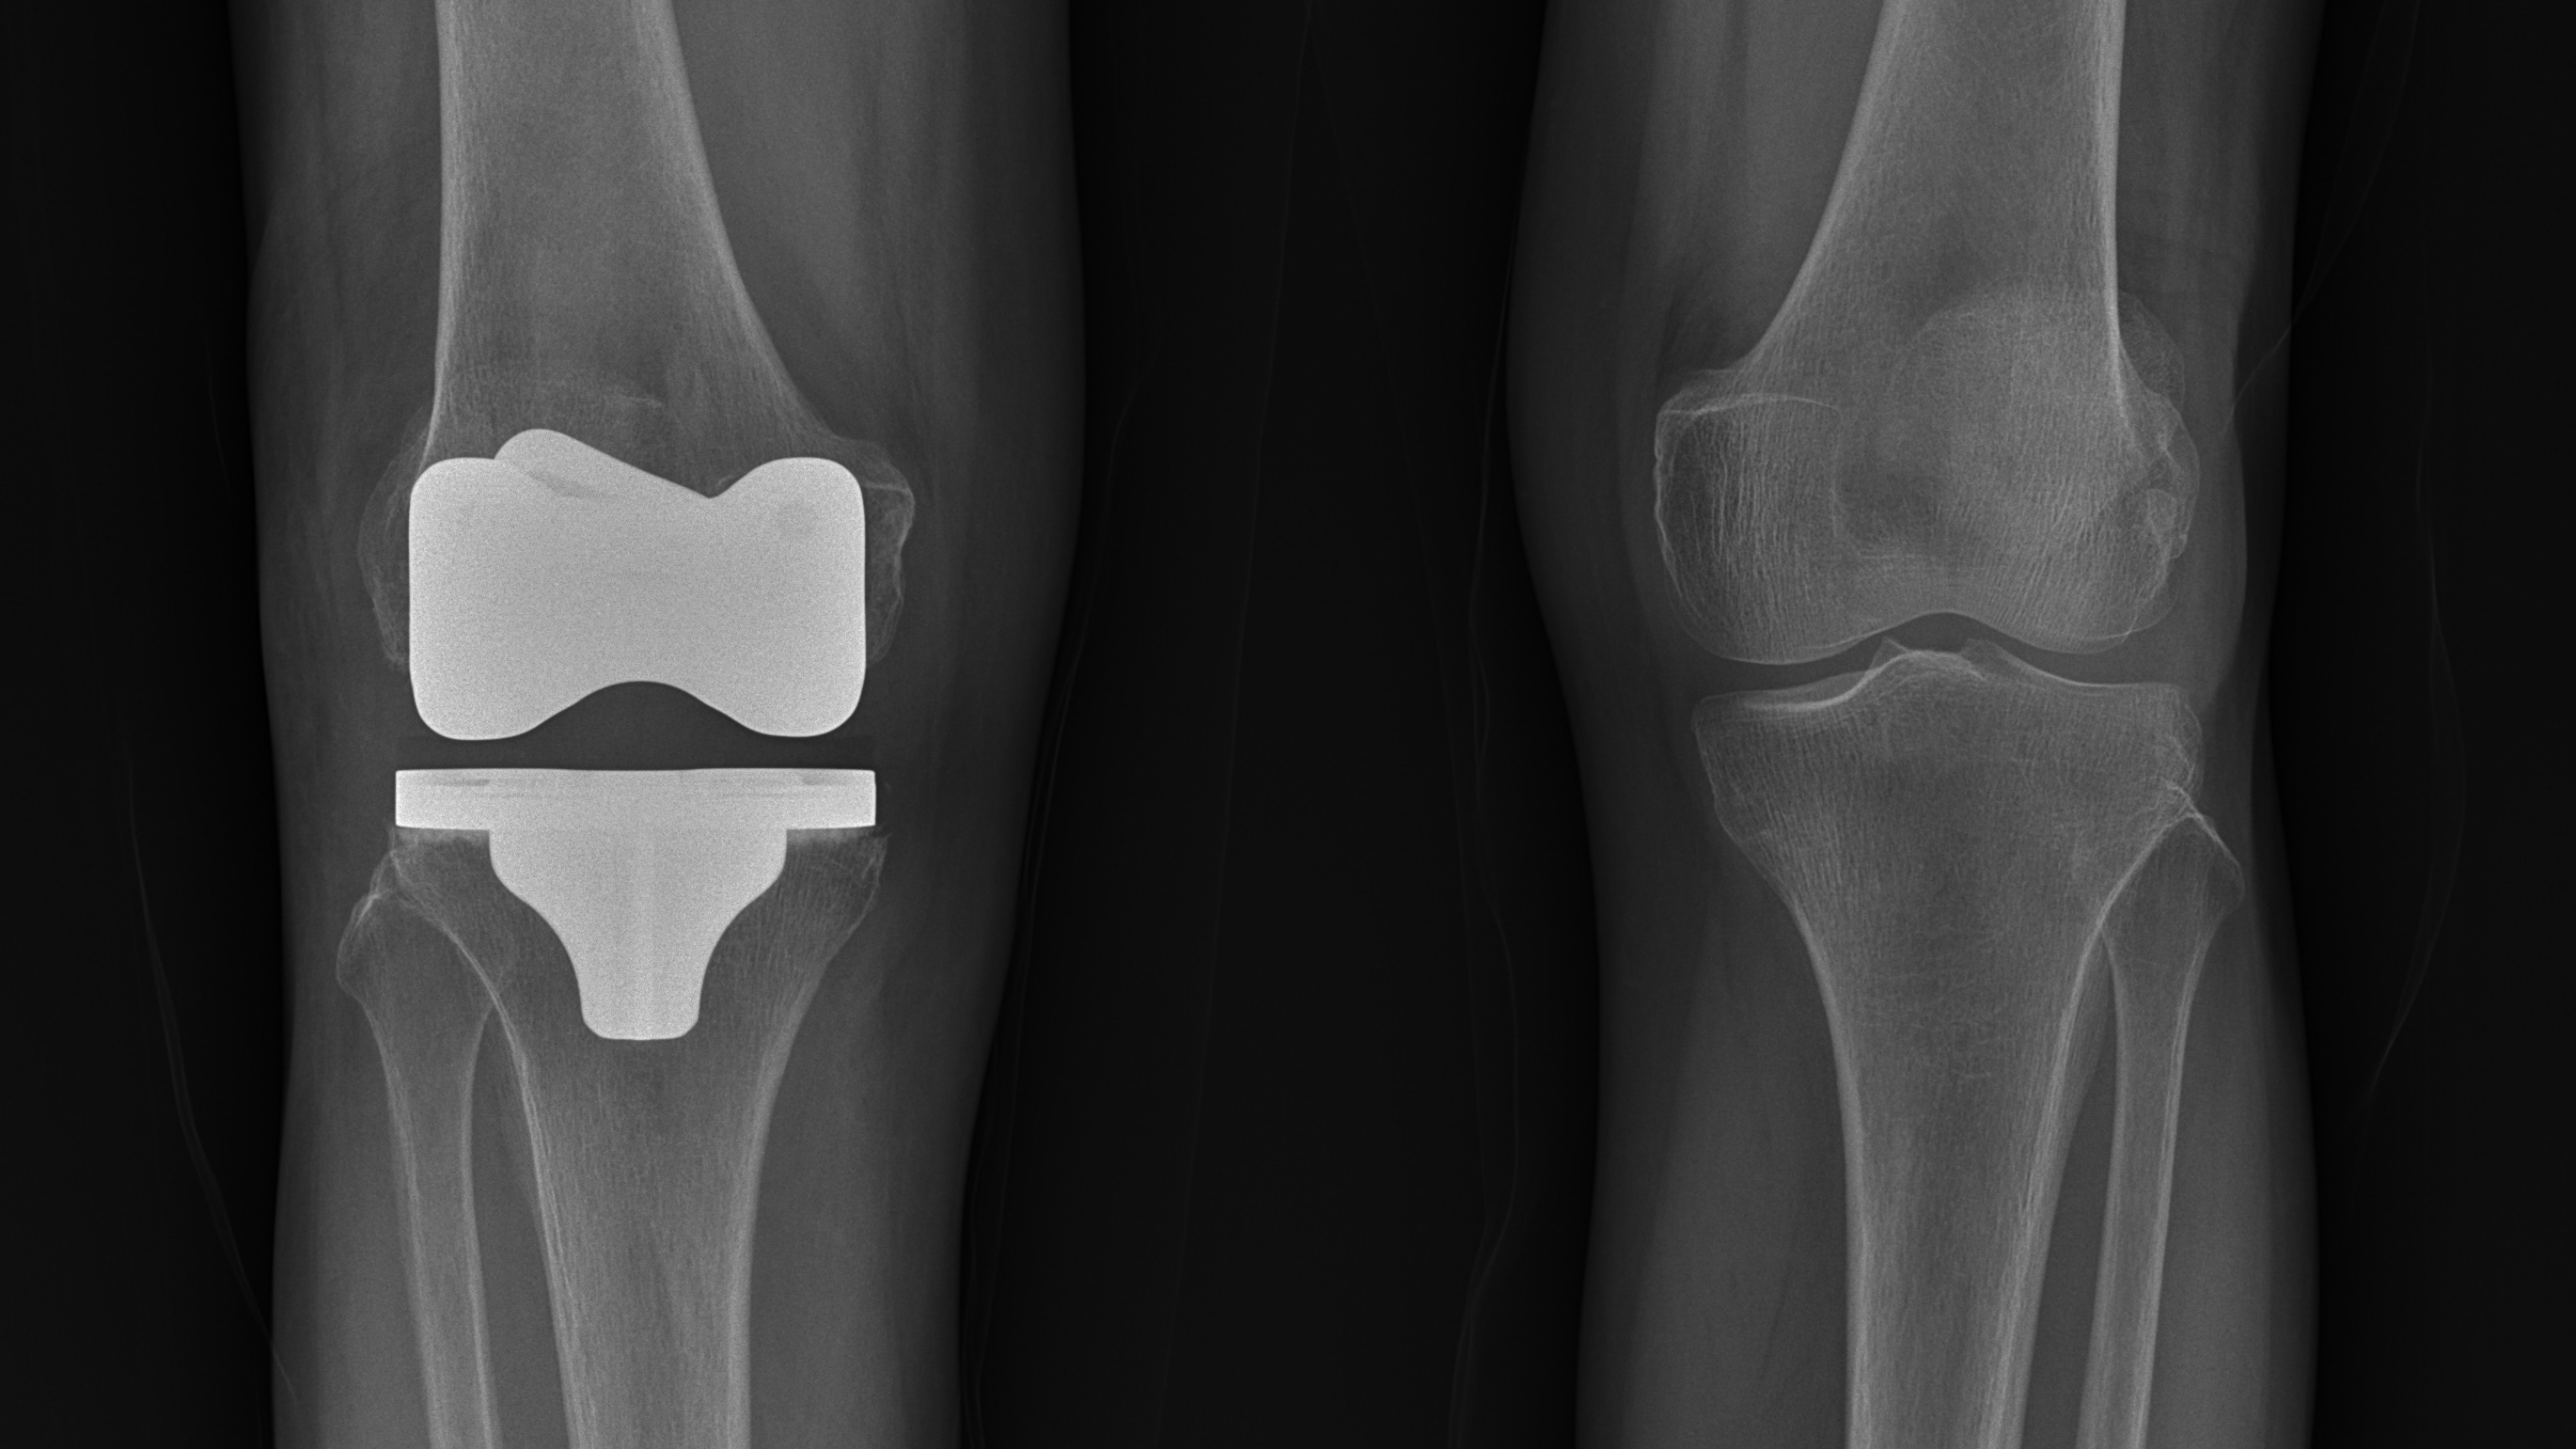

[의료진 칼럼]